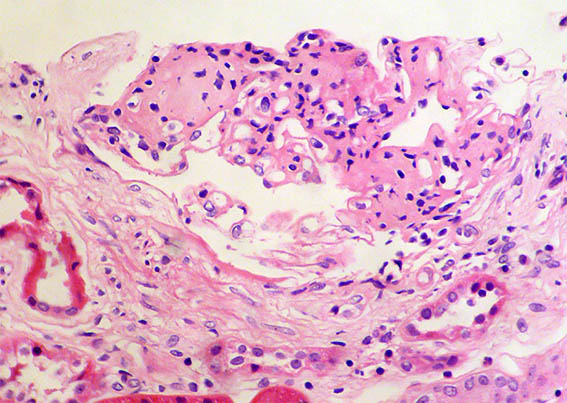

Figure 3.

H&E, X400. Lobulation.

Figure 4. H&E, X400. Nodules suggestive of Kimmelstiel-Wilson.